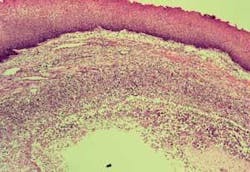

Significant microscopic characteristics: The ranula specimen is walled off by granulation tissue enclosing the mucin pool. Ductal dilation is evident with an inflammatory response (see Figure 2).